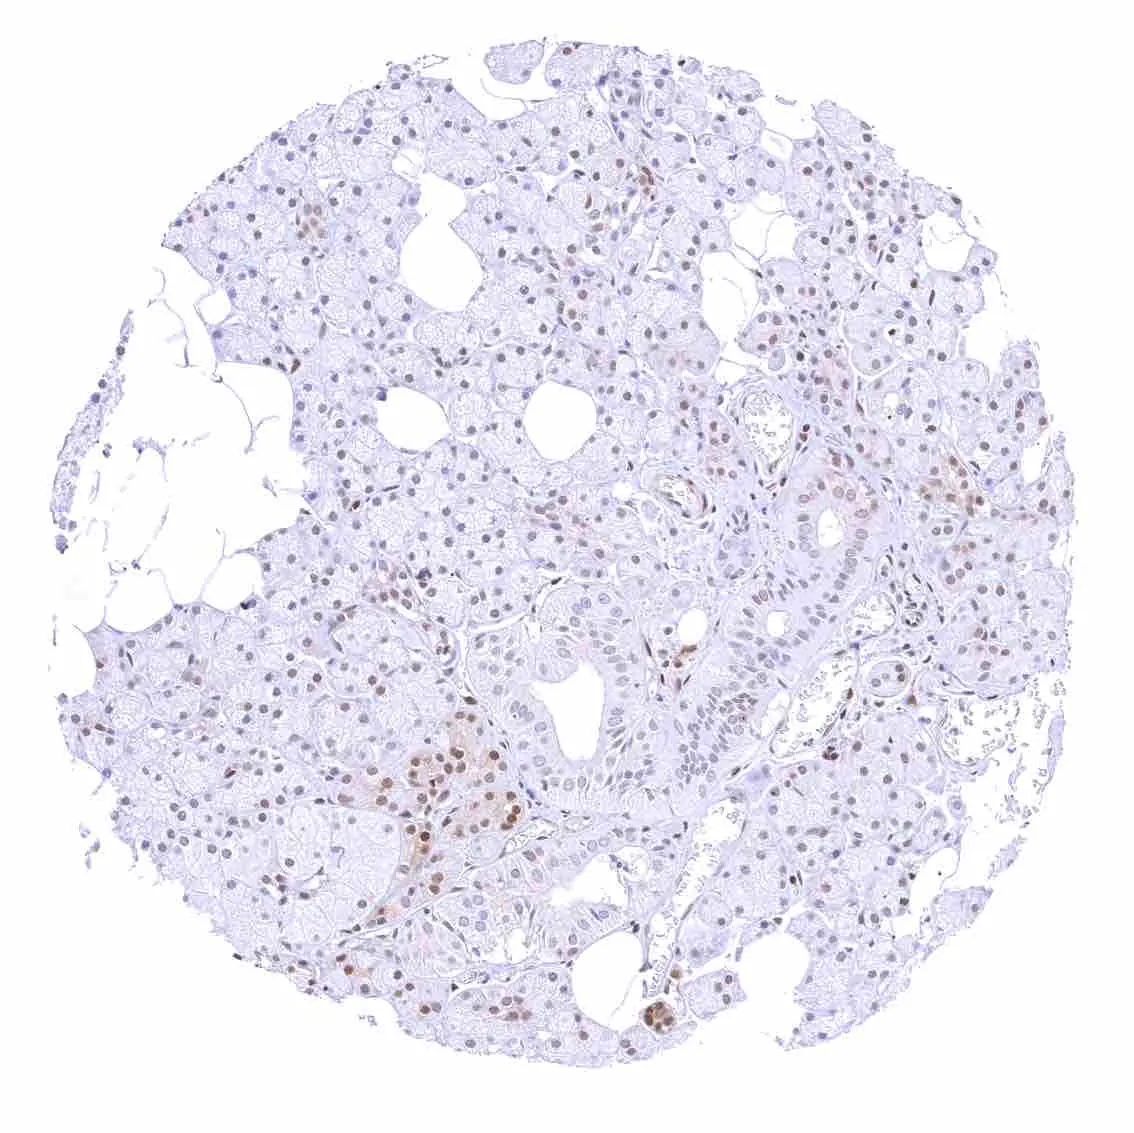

Pancreas – p27 staining is more common in islet cells than in acinar cells.